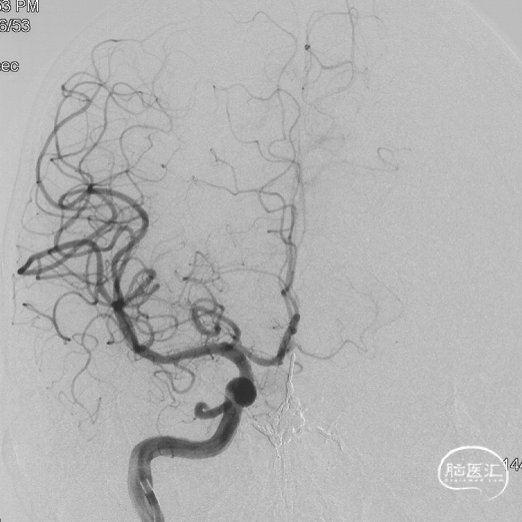

手术过程

Marathon微导管在Hybrid0.007微导丝导引下经左侧眼动脉超选至左侧筛前动脉,接近瘘口。

通过Marathon微导管超选造影,显示微导管楔入到靠近瘘口的动脉端。

通过Marathon微导管注入Onyx 18,胶向瘘口弥散,并弥散至镰前动脉。

停顿后进一步注射Onyx18,此时胶向对侧筛前动脉弥散,直至闭塞瘘口和引流静脉起始端。

最终造影瘘口完全不显影。

双侧脉络膜染色正常。